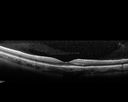

31 year old man with vision loss in the right eye more than the left eye. He has an anaplastic astrocytoma diagnosed 10/2017 the first one was 10/2014. These are different locations. They are treating them with Chemotherapy and Avastin. It might be that one might have spread from the other. He was clean for 3 years. He is on Avastin and Temozolomide but his blood counts have been good. December 2017 he had a herpes superficial infection in the right eye which responded to treatment. The last neurosurgery was October 2017. Going to Duke June 5 and seeing a neuroophthalmologist there. VA OD: Dcc20/40 PH20/25 NccJ5 VA OS: Dcc20/16 PH20/10 NccJ1+ His fundus is presumably nocardia, pneumocystis, aspergillis or cryptococcus. His LP was negative and he was tried on a course of antifungals. He was then lost to followup

Multifocal Choroiditis - Pneumocystis - aspergillis - cryptococcus606 views31 year old male with anaplastic astrocytoma on chemotherapy with mild vision loss in the right eye. LP did not reveal organism. He was placed on a trial of anti-fungal medications and lost to follow-up00000